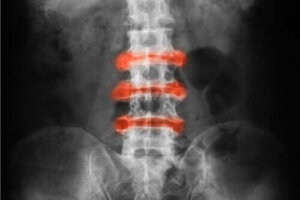

Ankyloserende spondylitt er inflammatorisk leddgikt som hovedsakelig forekommer i leddene i rygg og bekken. Akutte plager og stivhet har en tendens til å bli bedre med fysiske aktiviteter, og inaktivitet kan gjøre det verre.